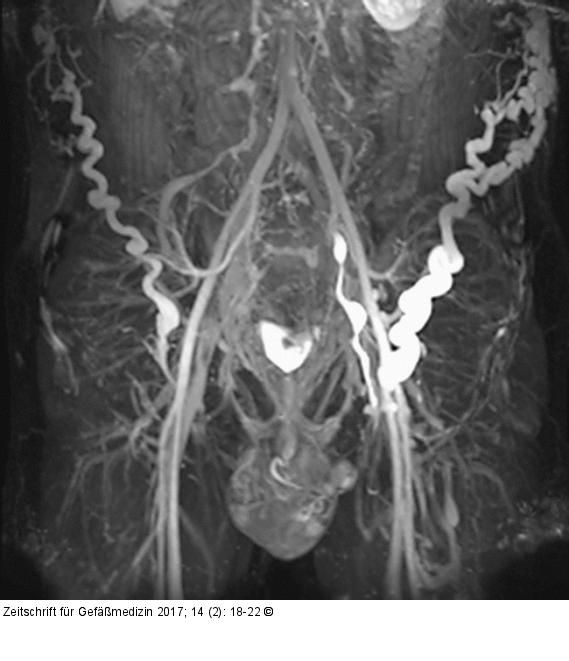

Abbildung 1: MR-Phlebographie MR-Phlebographie eines 25-jährigen Patienten mit schwerem postthrombotischen Syndrom und Obstruktion der infrarenalen V. cava sowie Beckenvenenstrombahn bds. Der venöse Abstrom erfolgt über zahlreiche Kollateralvenen der Bauchwand bzw. des Beckens. |

MR-Phlebographie eines 25-jährigen Patienten mit schwerem postthrombotischen Syndrom und Obstruktion der infrarenalen V. cava sowie Beckenvenenstrombahn bds. Der venöse Abstrom erfolgt über zahlreiche Kollateralvenen der Bauchwand bzw. des Beckens. |